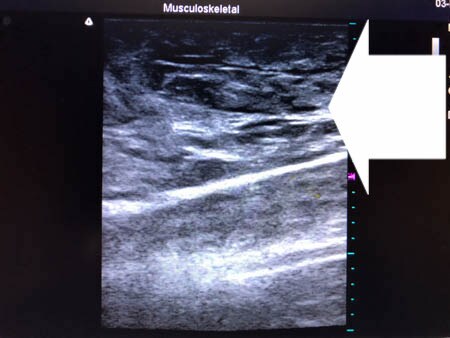

いつものように3Dタッチビュー(超音波)で

皮下脂肪層を評価してみましょう。

左太もも前面。